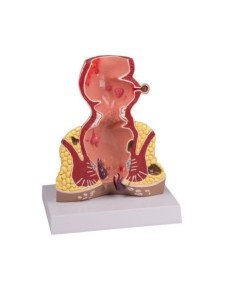

Erler Zimmer, modello anatomico di dente cariato, ingrandito di 10 volte D214